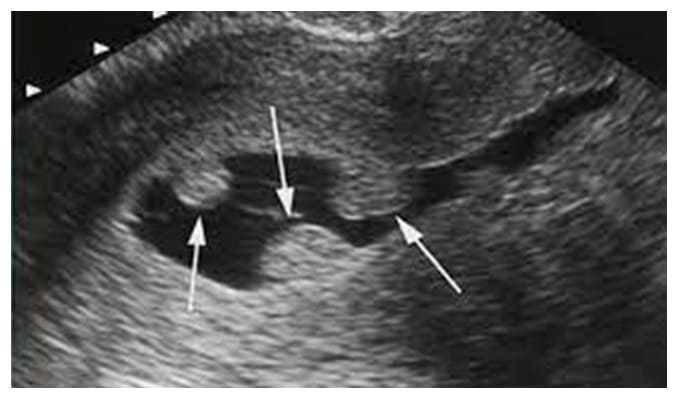

Son tumores sólidos blandos, que se desarrollan en la capa interna del útero (endometrio).

El crecimiento excesivo de las células en el revestimiento del útero (endometrio) produce la formación de pólipos uterinos, también conocidos como "pólipos endometriales". Estos pólipos no suelen ser malignos en su mayoría, aunque algunos sí pueden serlo o, con el tiempo, pueden malignizarse (pólipos precancerosos).